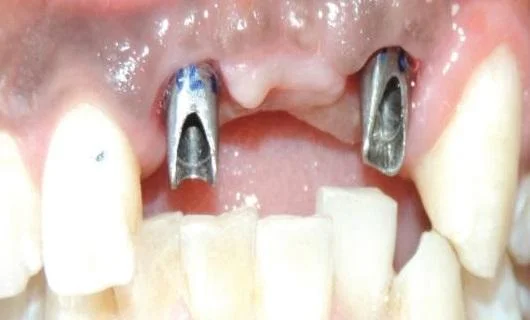

Feature 3: Reconstruction of the tooth crown according to anatomical standards using Customized Abutment.

The tooth crown not only transmits chewing forces and sensory feedback but also stabilizes the periodontal tissues. To optimize force transmission, crown shapes vary greatly between anterior and posterior teeth, as well as between upper and lower molars.

In traditional implant methods, prefabricated abutments with a single cylindrical shape and round cross-section are used. These differ significantly from the morphology of natural crowns and therefore cannot create ideal crown contours or fully perform the role of a natural crown.

Digital Customized Technology uses Customized Abutments that are individually manufactured to match the ideal anatomical morphology of each tooth and each person. Customized Abutments replicate the ideal crown morphology, providing strong support for periodontal tissues, optimal force transmission, and, thanks to advanced materials, allow the gingiva to directly attach to the abutment surface, creating a biological barrier that prevents bacteria from penetrating deeper structures.

All abutments are manufactured from pure titanium or monolithic zirconia using Computer Aided Manufacturing (CAM) technology, and the crowns are produced from multilayer monolithic zirconia.